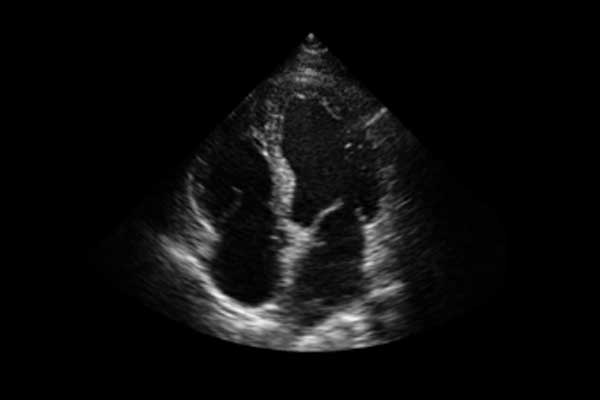

X3便携式彩色多普勒超声诊断系统是一款将小巧机身与卓越性能结合的便携产品。高度集成化的硬件模块,配合时尚前沿的人机工学设计打造了X3,如笔记本电脑般轻薄灵巧的机身、同时也赋予它突破体量限制的优异整机性能。轻便小巧,简单易用。图像清晰,X3可以随时随地满足您的使用需求。

X3搭载了丰富的探头群,可全面满足腹部、泌尿系统、浅表器官、妇科、产科、心脏及外周血管等常规领域应用。轻薄灵巧的主机机身、人性化的台车设计、实用的三探头扩展器、使得它无论在超声科还是在移动诊疗应用中都可以轻松应对。

轻巧灵便、功能全面的设计理念,使得X3在ICU床旁、急诊科等多科室应用游刃有余,为临床提供快速准确图像的同时,大大减轻医生的工作强度。